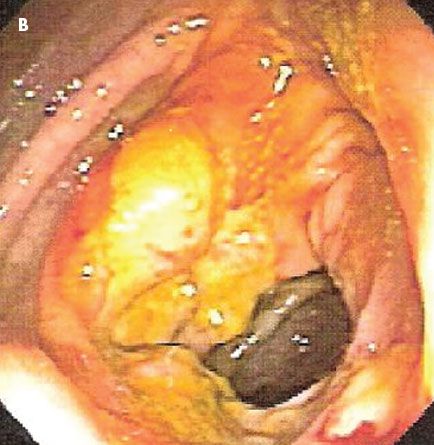

The patient had tenderness in the right upper quadrant, without signs of peritonism. A CT scan with contrast of the abdomen and pelvis demonstrated an apple core lesion (A). Colonoscopy revealed an ulcerated mass in the ascending colon, which strongly suggested malignancy (B). However, a biopsy specimen of the lesion showed only inflammatory changes with areas of ulceration (C).

It is becoming increasingly clear that NSAIDs, including salicylates, may adversely affect the colon as well as the upper GI tract.1,2 They may cause nonspecific colitis or exacerbate a preexisting colonic disease. Presenting features include abdominal pain, weight loss, diarrhea (bloody or nonbloody), and iron deficiency anemia. Colonoscopy may show inflammation, ulceration, or stricture. Histology often shows a nonspecific colitis or pattern similar to that of ischemic colitis.3